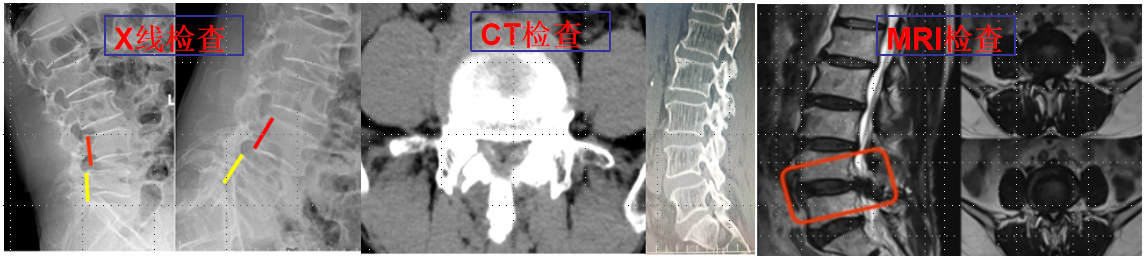

②椎間孔鏡技術(shù):科室常規(guī)熟練開展椎間孔鏡技術(shù)治療頸、胸、腰椎椎間盤突出癥、椎管狹窄癥、椎管黃韌帶骨化等。

利用椎間孔鏡從患者腰椎側(cè)方或者后方進(jìn)入達(dá)到椎間盤突出或者其他病變部位,用專用工具將突出(脫出)的椎間盤組織或病變?nèi)〕觯ㄈコ亩_(dá)到治療椎間盤突出或者椎管狹窄的目的。它的優(yōu)勢(shì)在于:局部麻醉、微創(chuàng)、切口小(僅約7mm),出血少,恢復(fù)快(第二天即可佩戴硬腰圍下地)及療效好。